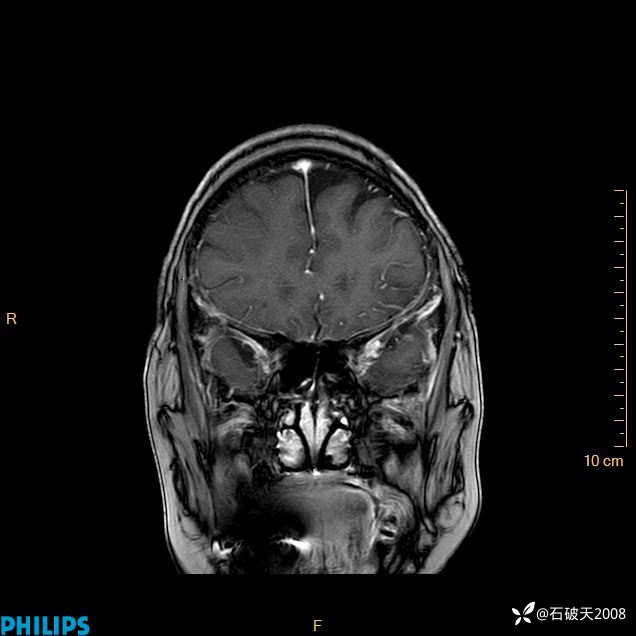

2024.2.21MR

增强冠状位